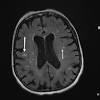

Risikofaktorer For Frontotemporal Demens Tidsskrift For Den Norske Legeforening

Risikofaktorer For Frontotemporal Demens Tidsskrift For Den Norske Legeforening from tidsskriftet.no